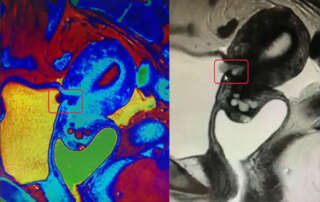

A rare case of a vesicouterine fistula managed by 3 minimally invasive approaches (Video Article)

DOI: 10.36205/trocarvid4.2022001